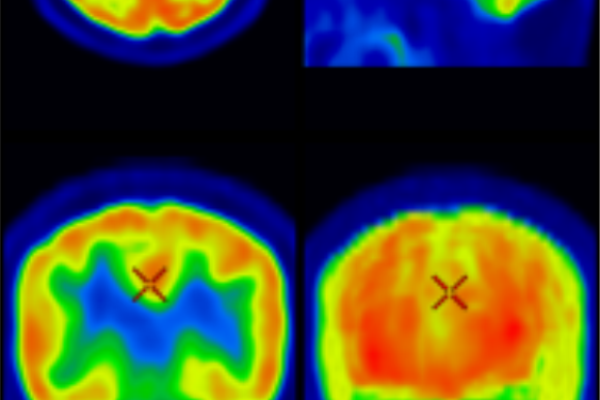

BRAIN-PET

Brain PET

Brain PET imaging is a highly advanced diagnostic tool used to assess the brain’s metabolic activity and function. It plays a crucial role in the early detection and evaluation of neurological conditions such as Alzheimer’s disease, various forms of dementia, epilepsy, and movement disorders like Parkinson’s disease. By analyzing how different areas of the brain process glucose, Brain PET helps distinguish between types of cognitive decline, assess disease progression, and guide treatment planning with greater accuracy than structural imaging alone.

Key Indications:

• Early detection of Alzheimer’s disease and other dementias

• Evaluation of movement disorders (e.g., Parkinsonism)

• Pre-surgical evaluation of epilepsy

• Assessment of brain tumors or infections